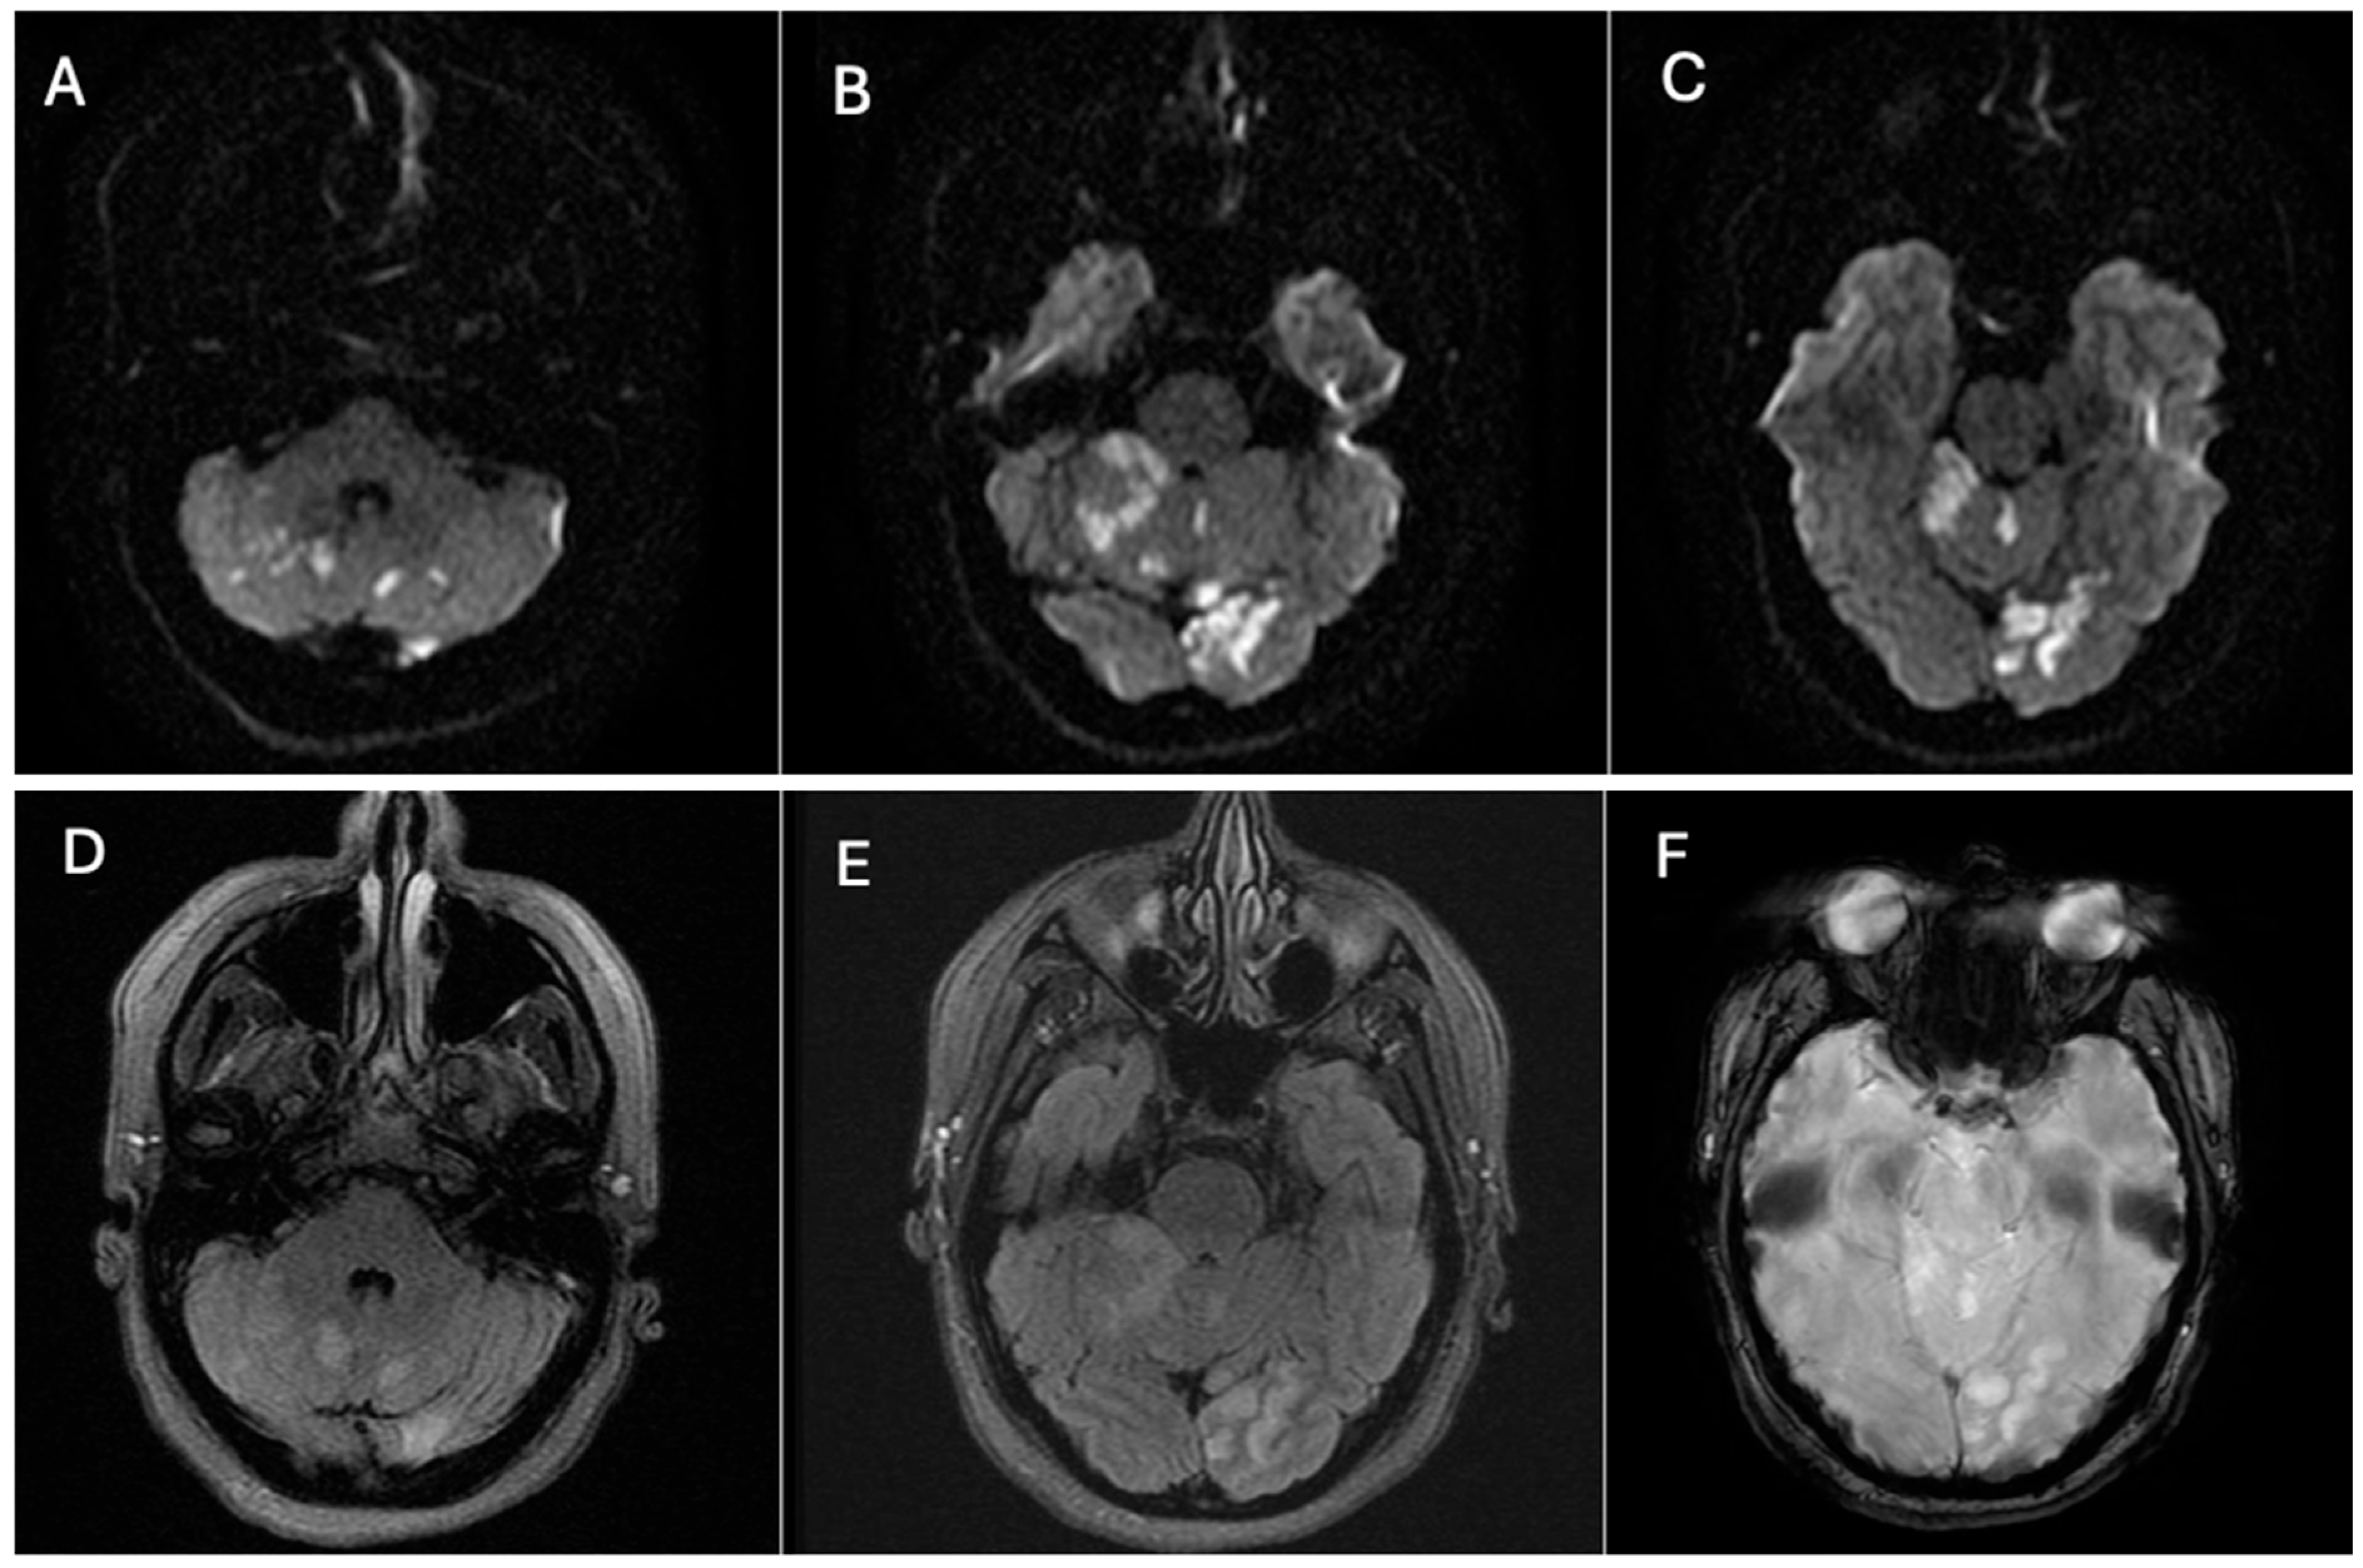

Digital subtraction angiography (DSA) confirmed the presence of a dissecting fusiform aneurysm of the left vertebral artery at the V1–V2 junction, associated with a contained pseudoaneurysm. The true aneurysmal dilation measured 18 × 15 mm, while the pseudoaneurysm was not quantified separately. The V1 (pre-foraminal), V3 (extradural), V4 (intracranial) segments, and the basilar artery were normal. A right P1 segment agenesis with a fetal-type posterior communicating artery was also observed (Figure 3). The apparent discrepancy in aneurysm size between CTA and DSA can be explained by the different imaging principles: CTA captured both the intraluminal aneurysmal dilation and the adjacent perivascular hematoma/pseudoaneurysmal component, whereas DSA more accurately reflected the true intraluminal dimensions of the dissecting aneurysm.

Figure 3. Digital subtraction angiography (DSA) of the left vertebral artery demonstrating a dissecting fusiform aneurysm at the V1–V2 junction with an associated contained pseudoaneurysm. The fusiform aneurysmal dilation measured approximately 18 × 15 mm; the pseudoaneurysm was not quantified separately. The procedure was performed after intra-arterial administration of 10–15 mL of non-ionic iodinated contrast medium (Iohexol, Omnipaque® 300 mg I/mL) per injection, delivered at an injection rate of approximately 4–6 mL/s, with high temporal resolution acquisitions (2–3 frames/s) during the arterial phase: (A) Oblique projection after intra-arterial contrast administration showing the dissecting fusiform aneurysm. (B) Three-dimensional reconstruction confirming the aneurysmal morphology and vessel anatomy. The aneurysm is indicated by red arrows, while the mural defect is highlighted by a red arrowhead. The remaining vertebrobasilar segments were unremarkable. Source: patient’s medical record, published with prior authorization.